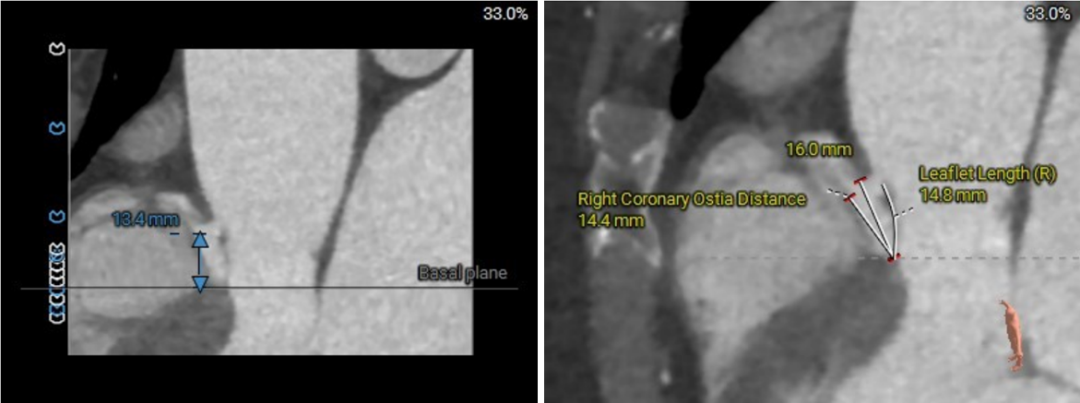

主动脉根部评估

四叶式主动脉瓣,右无间窦体发育较小且窦底高于瓣环平面约6mm;

瓣环上结构测量

收缩期瓣上结构

收缩期瓣上可提供4~6mm筒状区域。

舒张期瓣上结构

舒张期瓣上5mm内区域均小于收缩瓣环径;

该病例的瓣上结构可提供的辅助锚定区域较长,有利于瓣膜的辅助锚定。

流出道结构测量

收缩期流出道结构

收缩期流出道可提供6mm筒状区域。

舒张期流出道结构

舒张期流出道约3mm筒状区域;

流出道收缩期和舒张期可锚定区域波动较大,整体约4mm辅助锚定区域。

冠脉高度、瓣叶长度及左室内径

左冠高度:7.1mm;右冠高度:13.4mm;

左冠-窦底距:9.7mm;右冠-窦底距:14.4mm;

左冠瓣长度:12.3mm;右冠瓣长度:14.8mm;

左冠水平高度较低,开口内径较大,瓣叶略长,LCC至对合缘距离约30mm,存在一定左冠阻塞风险。

左室室间隔基底部肌性凸起,增加了流出道锚定有利因素。